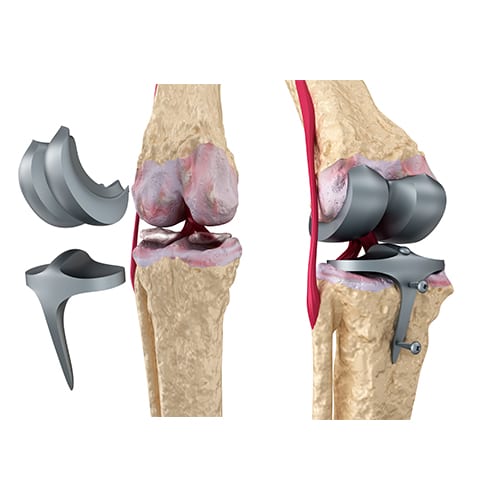

החלפה מלאה של מפרק הברך – Total Knee Replacement:

ניתוח קונבנציונלי: ניתוח החלפה מלאה של מפרק הברך Total Knee Replacement – הוא הניתוח השכיח ביותר ובו מדווחים אחוזי ההצלחה המשמעותיים ביותר – שיעור הצלחה של מעל 90%. בניתוח מוחלפים המשטחים המפרקיים השחוקים במשתל מתכתי. אורך החיים של המשתל הוא מעל 15 שנה ורמת הסיבוכים בניתוח, באופן כללי, נמוכה.

החלפה חלקית של מפרק הברך – Uni Condylar Knee Replacement:

למקרים בהם השחיקה הסחוסית מוגבלת למדור אחד של הברך, מצב המאפיין אוסטאוארטאיטיס בעשורי חיים מוקדמים יחסית. הניתוח "קטן" יותר ומותיר רקמה ביולוגית טבעית בריאה בברך המנותחת.